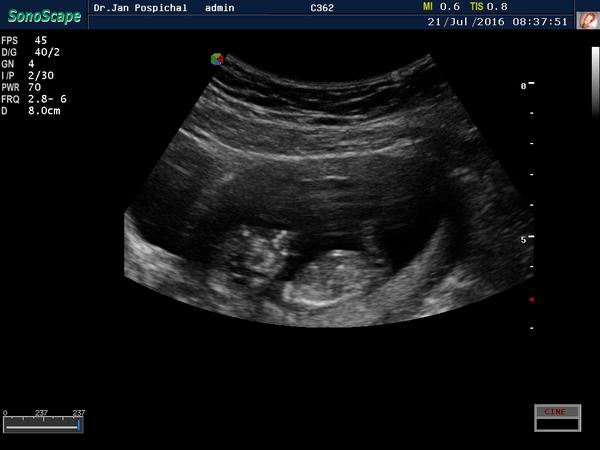

Je to holčička nebo chlapeček? Foto ultrazvuku

Ahoj maminky a budoucí maminky 😉 Prosím, poradila byste mi některá, co vidíte na fotce z ultrazvuku ve 20. týdnu za pohlaví? Určitě jste foteček viděly už mraky, proto vás žádám o radu...Nechci nikoho ovlivnit, proto svůj tip řeknu později 🙂 Děkuju moc!!!

@matylda123 kavove zrno tam neni. Bych ti to zakrouzkovala,ale z mobilu to nejde. Muj tata takhle na utz poznal diky mocove trubici nasi treti dcerku v 16 tt,primo v primem prenosu mi ukazal mocovou trubici a jak zrovnw cura a ta trubice byla rovne a koncila spolu s telem. Tady jde sikmo nahoru a jeste vystupuje z tela. Aspon jsem to vyfotila bliz. Tak jsem zvedava 🙂 pri dalsim utz nspis. A fotku zespoda nemas?

@matylda123 tak jeste super vyrez,co presne myslim 🙂

@estrellita moc díky za info 🙂 ne jinou fotku nemám... V úterý dám vědět, ale taky si myslím, že to vypadá na pinďoura 🙂

@estrellita ještě mě napadlo že to je vyfoceny rychlý pohyb ruky dolů...No v úterý se to dozvíme 🙂

@matylda123 ruka vede niz,sleduj kost od raminka,ta je hezky videt.

Je to kluk holky 🙂

Hlásím,že máme potvrzeného Vojtíška a je to prý pořádný bobíšek 🙂 hlavně,že se má v bříšku dobře 🙂

@matylda123 tak opravdu jsem videla mocovou trubici,tata mi to vcera potvrdil,ze ano,ze to tak vypada,ale on neni gyn,tak rekl,ze kdyz ten utz nevidi v realnem case,ze samozrejme jiste to ruct nemuze. Tak mu to reknu 🙂

@matylda123 ale jinak krasna fotka